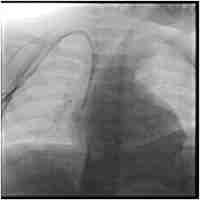

| Abstract | A 20-year-old woman admitted with an aspirin overdose was encephalopathic and was intubated for airway protection. Under sonographic guidance, a right internal jugular central venous catheter was inserted for volume resuscitation. She was agitated and required treatment with a propofol infusion. Her salicylate levels improved and she was successfully extubated 12 h after intubation. One day later she developed severe dyspnoea and a right-sided pleural effusion and required immediate reintubation. The effusion was drained and was consistent with a chylothorax. A CT scan of the chest revealed that the central venous catheter traversed the mediastinum with its tip in the right pleural space. The propofol infusion was draining into the pleural space. A video-assisted thoracoscopic surgery was performed to drain the pleural effusion and repair the punctured vessel. She was extubated within a day and discharged home 1 day later without any pleural fluid. |